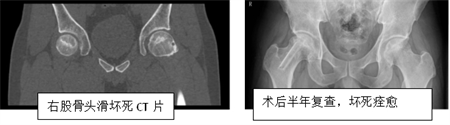

第二项是显微吻合血管腓骨瓣移植“保头”治疗股骨头坏死。骨头坏死,是临床上常见多发病,病程的早中期,治疗手段多样,有中医中药、髓芯减压、带生长因子的人工骨骨移植等等,其疗效不肯定,在诸多治疗方法中,带血管骨瓣移植,其疗效肯定。骨外二科在2023年,对多例早中期股骨头缺血性坏死病例,进行显微吻合血管腓骨移植手术,取得了较好疗效。并于2024年1月18日顺利通过评审验收。该方案适用于中青年的股骨头坏死早中期阶段,通过有效“保头”手术治疗,患者很可能彻底告别人工髋关节置换手术。